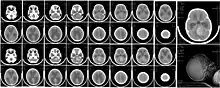

| CT scan, showing a tumorous mass in the posterior fossa, giving rise to obstructive hydrocephalus, in a six-year-old girl | |